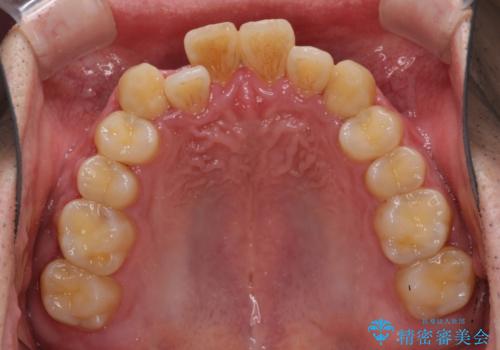

前歯のクロスバイトを改善 インビザラインによる矯正治療

- 前歯のクロスバイトを気にして来院された患者様です。

デコボコやクロスバイトが散見されたため、IPR(歯と歯の間を削る)によってスペースを獲得できるように設計し、インビザラインにより治療を行うこととしました。

今回は、ワイヤー装置を併用することなく治療を行い、トラブルなく、満足のいく歯列に整えることができました。

矯正治療の途中でホームホワイトニングを併用され、術前とは見違えるほどきれいな口元となりました。